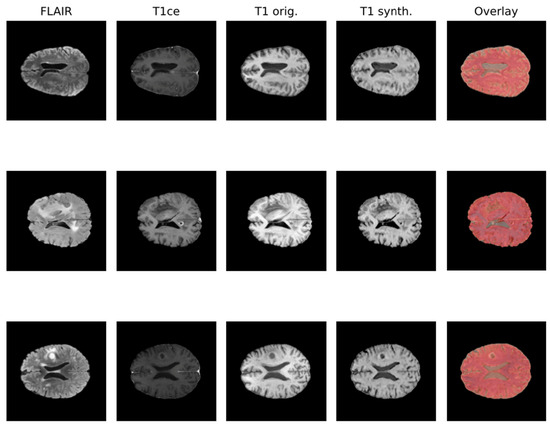

- Wu, J.; Guo, D.; Wang, L.; Yang, S.; Zheng, Y.; Shapey, J.; Vercauteren, T.; Bisdas, S.; Bradford, R.; Saeed, S.; et al. TISS-net: Brain tumor image synthesis and segmentation using cascaded dual-task networks and error-prediction consistency. Neurocomputing 2023, 544, 126295. [Google Scholar] [CrossRef]

- Conte, G.M.; Weston, A.D.; Vogelsang, D.C.; Philbrick, K.A.; Cai, J.C.; Barbera, M.; Sanvito, F.; Lachance, D.H.; Jenkins, R.B.; Tobin, W.O.; et al. Generative Adversarial Networks to Synthesize Missing T1 and FLAIR MRI Sequences for Use in a Multisequence Brain Tumor Segmentation Model. Radiology 2021, 299, 313–323. [Google Scholar] [CrossRef] [PubMed]